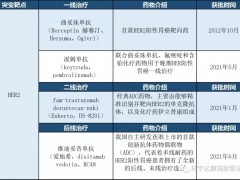

适合患者:NTRK1/2/3、ROS1或ALK基因重排突变的实体瘤

适合患者:只要存在NTRK融合,不限癌种

适合患者:晚期恶性实体瘤

适合患者:NTRK基因融合

适合患者:标准治疗失败或无标准治疗方案的晚期实体肿瘤患者

适合患者:晚期实体瘤患者

适合患者:晚期或转移性实体瘤